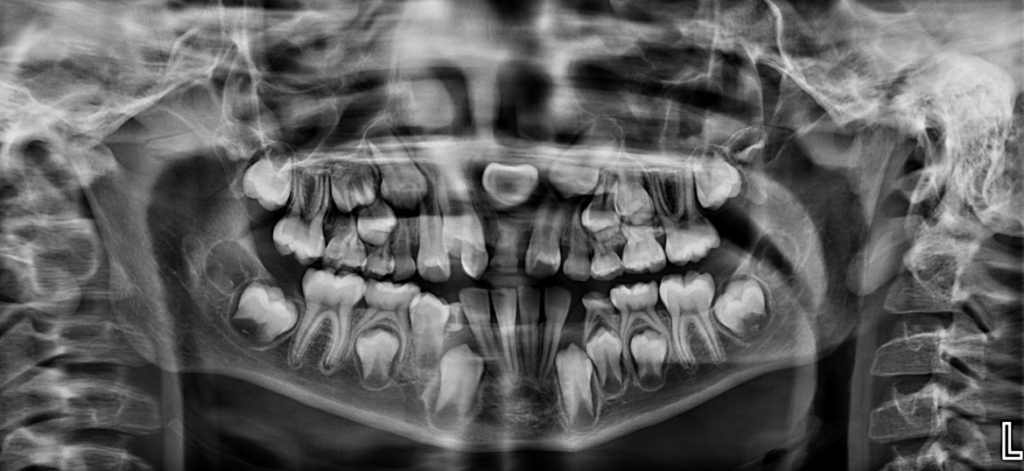

Radiografia Panorámica

A la evaluación de la radiografía panorámica se observa terceros molares en formación, múltiples piezas deciduas con lesiones cariosas, sin embargo, lo que llama la atención es la zona anterosuperior donde observamos la presencia de una pieza supernumeraria extraósea que ocasiona la impactación y el retraso en la erupción de la pieza 11, asimismo se observa la inclusión de la pieza 21 en posición transversal y la persistencia de la pieza 61.